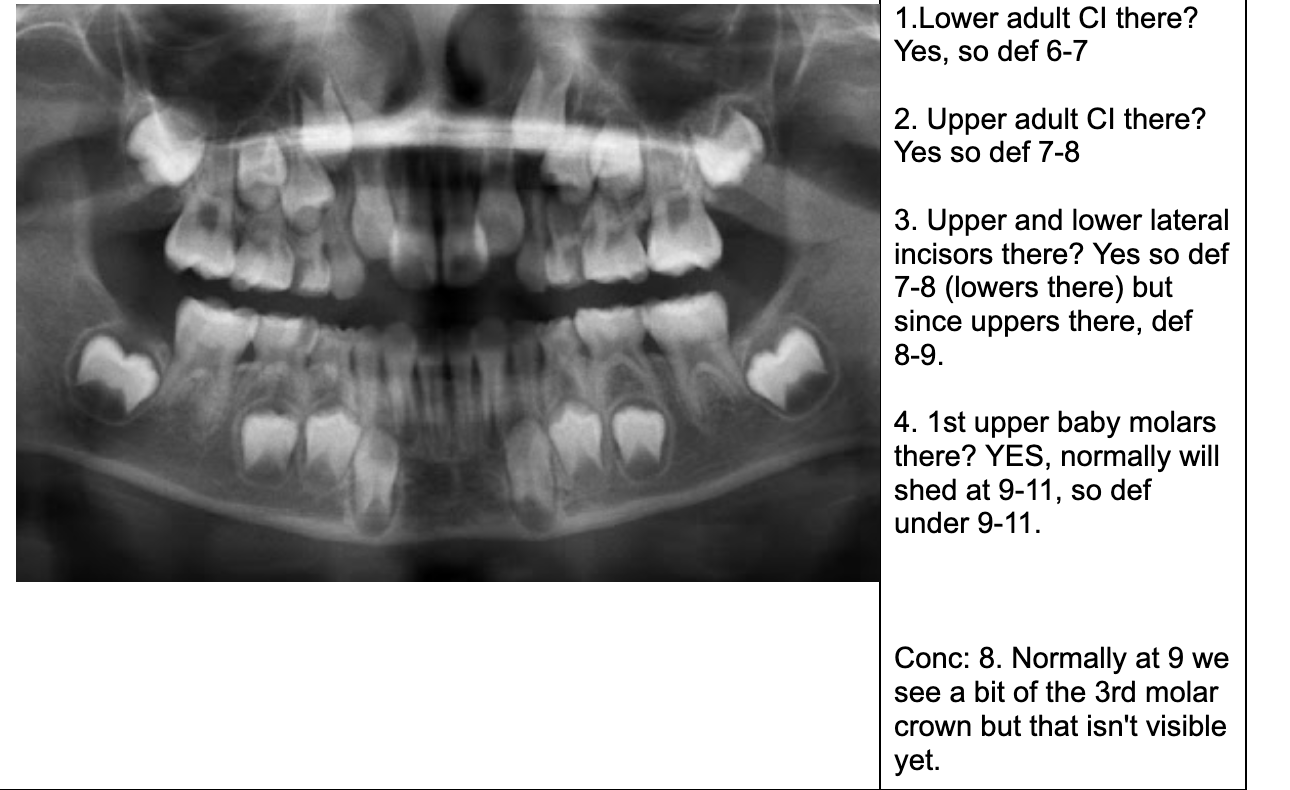

1.lower adult CI there? YES, so def 6-7

1. Upper Ad. Ci there? NO, so either 6-7 or under

Last molar crown not really formed so 6?

NOTE- THE 8’s - crown starts developing at 9 yo.